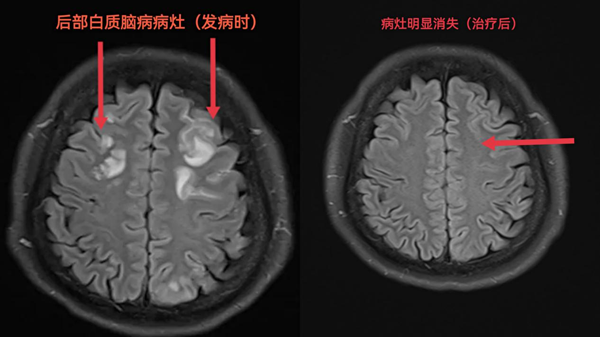

一日,神经内科病房传来一阵急促的电话铃声,值班医师接通电话后得知,一名合并妊娠期高血压和2型糖尿病的34岁孕妇于家中突然出现视物模糊,急至产科住院后需神经内科协助共同诊治,神经内科宋文良主任迅速赶到产科病房查看病人,考虑患者现血压较高,不排除急性脑血管病可能,建议其立即行颅脑磁共振检查。随后颅脑磁共振提示:可逆性后部白质脑病、SWI序列示蛛网膜下腔出血(少量)。诊断明确后,经多学科共同会诊决定,立即将胎儿剖出,术后将产妇转至神经内科专科治疗,同时保证母婴安全。在神经科病房,我们通过颅脑MRA、MRV等一系列检查,排出了患者脑动脉畸形及大脑静脉血栓的可能,反复讨论病情后认为,此次蛛网膜下腔出血是由于后部白质脑病引起的脑血管痉挛及水肿而导致的渗血所致。产妇住院初期先后又出现头痛、双上肢麻木等症状,经过了十余天严格的控制血压、防止脑血管痉挛、绝对卧床、营养脑细胞等专业治疗后,患者视物模糊完全消失,头痛缓解,双上肢麻木明显改善,复查颅脑磁共振提示后部白质脑病病灶明显好转,蛛网膜下腔出血已完全吸收(图1、2),次日,产妇终于顺利出院与刚出生的宝宝团聚,出院时神经科医护人员反复叮嘱病人,一定监测血压,按时复诊,出院时,患者和家属再三对医生护士们表示了赞许和感谢。

图1

图2